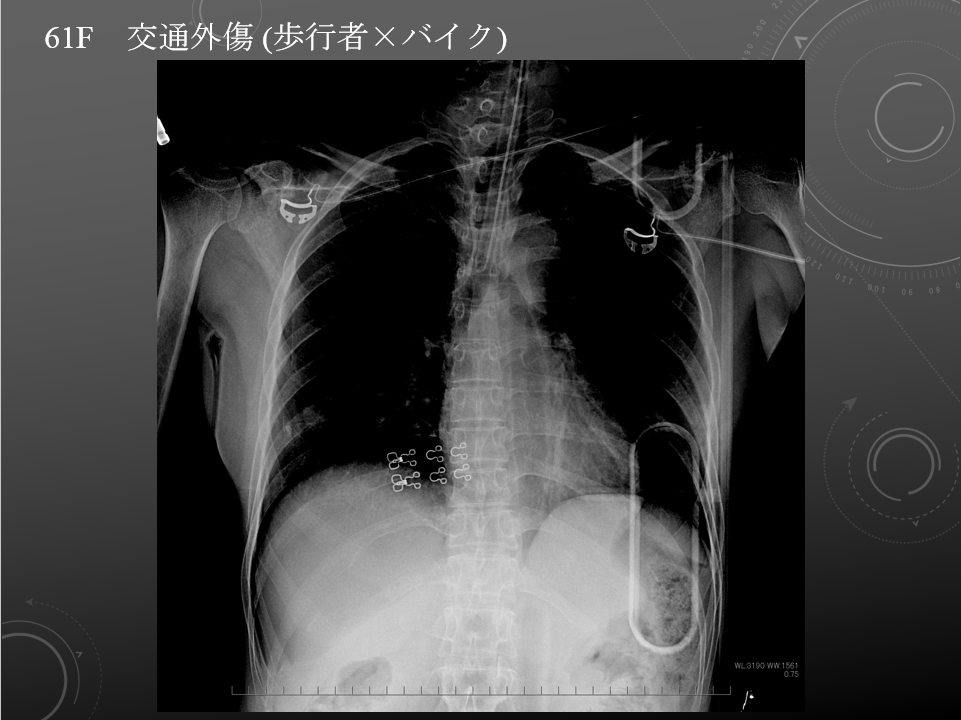

61F 交通外傷 オートバイ×歩行者 歩行者

歩行者

オートバイ 30-40km/hr 接触後約6m引きずられた

胸部臥位単純写真

比較画像はありません。

気管挿管後です。右片肺挿管に近い状況です。

右気胸が認められます。

左肺野および心縦隔陰影に異常所見は明らかではありません。

大量胸水貯留所見は認められません。

同日 CT で認められている右鎖骨遠位部および、第4-7肋骨骨折が確認されます。第11胸椎骨折は、本検査上指摘困難です。

右気胸、右多発肋骨骨折、右鎖骨骨折。

気管挿管後:右片肺挿管に近い状況です。

61F 交通外傷 オートバイ×歩行者 歩行者

歩行者

オートバイ 30-40km/hr 接触後約6m引きずられた

胸部臥位単純写真

比較画像はありません。

気管挿管後です。右片肺挿管に近い状況です。

右気胸が認められます。

左肺野および心縦隔陰影に異常所見は明らかではありません。

大量胸水貯留所見は認められません。

同日 CT で認められている右鎖骨遠位部および、第4-7肋骨骨折が確認されます。第11胸椎骨折は、本検査上指摘困難です。

右気胸、右多発肋骨骨折、右鎖骨骨折。

気管挿管後:右片肺挿管に近い状況です。

高エネルギー外傷精査

歩行者 vs 原付バイクの交通外傷 搬送後舌根沈下あり、気管挿管された。